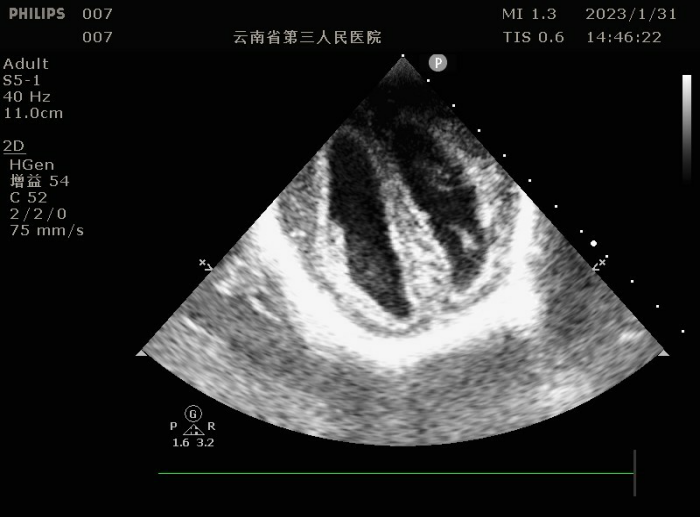

小儿颅脑超声检查是通过超声仪器,利用尚未闭合的囟门(如前囟、乳突囟、后囟等)作为声窗,对颅内结构进行扫描和观察。这种方法可以清晰地显示大脑、小脑、脑干等重要结构,以及颅内血管的情况,是一项可以与头颅核磁共振相媲美的检查方式。

超声检查能够帮助医生早期发现颅内出血、脑积水、脑损伤、感染等疾病,为临床治疗提供重要依据。

(颅脑超声图)